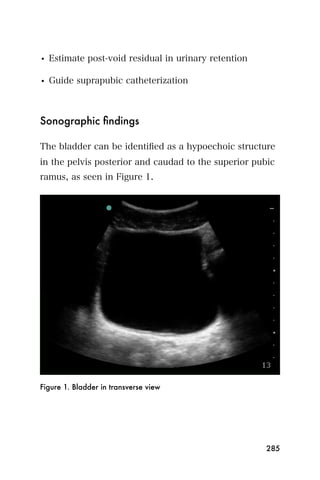

center that is the endometrium.

Figure 3. The bladder (*) and empty uterus (arrow)

An empty uterus may cause the clinician to worry about

an ectopic pregnancy. A ruptured ectopic pregnancy

blood may extend into the abdomen, so it is important

107

to look for blood within the abdomen as well as the